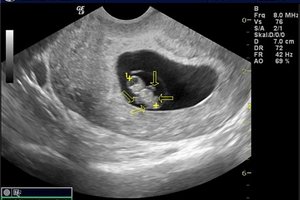

УЗД на такому терміні призначається рідко (зазвичай для підтвердження факту вагітності). Серцебиття дитини видно чітко, якщо у вас двійня - діагноз ставиться без сумнівів.

Якщо у вас термін середина другого місяця по акушерському календарю, то дізнатися кількість дітей не складно. Гінеколог може запідозрити, що там двійня вже при звичайному огляді на кріслі, так як матка виразно більше норми на вказаному періоді перебування в положенні. У цьому випадку вас направлять на УЗД для підтвердження діагнозу.